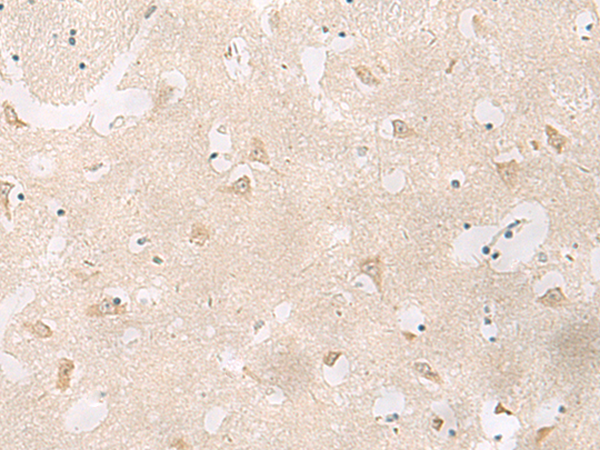

分类: 科研抗体货号: P13536别名: GRP; HSPC159应用: IHC反应种属: Human, Mouse